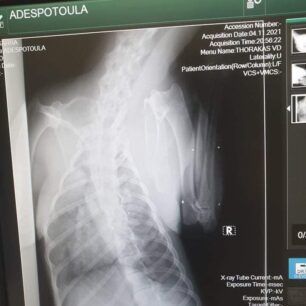

Το ζώο χειρουργήθηκε στις 9 Νοεμβρίου καθώς μεταξύ άλλων είχε και πυομήτρα. Οι ακτινογραφίες, που έβγαλε στην κλινική έδειξαν και τα πολλά σκάγια στο κορμί του – δηλαδή έχει πυροβοληθεί από κυνηγό – καθώς και το κάταγμα κνήμης και περόνης στο πόδι, το οποίο αντιμετωπίστηκε με νάρθηκα, αλλά και ο υγρό στον πνεύμονα (το όποιο αφαιρέθηκε με παρακέντηση). Είχε επίσης και εσωτερική αιμορραγία στην κοιλιακή χώρα.